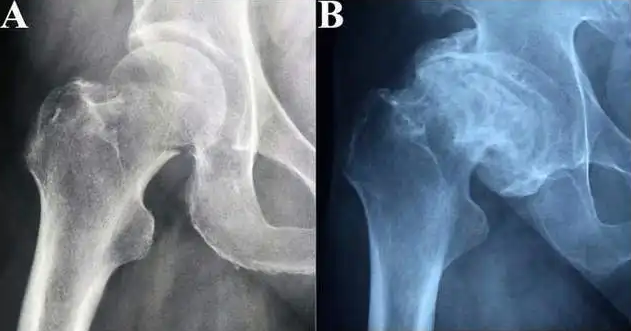

股骨缺血性坏死的影像学特点

在股骨头的承重面塌陷前即缺血性坏死的早期阶段作出诊断是非常有益的。缺血性坏死的早期X线表现是相对硬化,它发生在股骨头,与周围血管性的骨吸收有关。有时可能表现股骨头承重部分的轻微塌陷,这在蛙式位片上容易发现。MRI较X线更容易显示早期的缺血性坏死,有些特殊的征象可明确诊断,但不是所有MRI上髋关节信号异常都是缺血性坏死。MRI在鉴别正常与异常的髋关节的特异度为98%,但在区别缺血性坏死和非缺血性坏死时的特异度仅为85%。结合X线表现来解释MRI表现是有意义的。早期成人股骨头缺血性坏死的主要 CT征象是1)股骨头骨小梁呈星芒状扭曲,增粗;2)股骨头斑片、斑点状及条状骨质硬化或软骨下致密线;3)软骨下骨质微断裂、新月征、股骨头微陷。